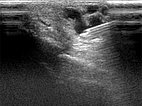

Perkutanes, sonograhisch gesteuertes Vorschieben der Punktionsnadel in die Drainagevene der digitalen AVM.

Nach Embolisation jetzt deutlich echoreiche Formationen mit dorsalem Schallschatten im Gefäß durch das Embolisat nach Auffüllen des AVM Nidus.